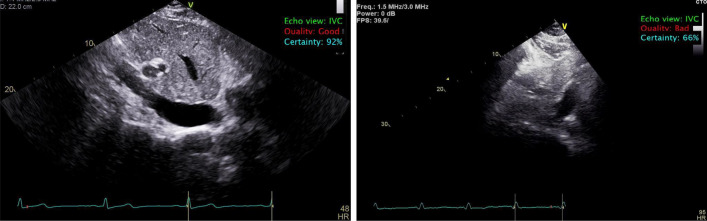

Current noninvasive estimation of right atrial pressure (RAP) by inferior vena cava (IVC) measurement during echocardiography may have significant inter-rater variability due to different levels of observers' experience. Therefore, there is a need to develop new approaches to decrease the variability of IVC analysis and RAP estimation. This study aims to develop a fully automated artificial intelligence (AI)-based system for automated IVC analysis and RAP estimation. We presented a multi-stage AI system to identify the IVC view, select good quality images, delineate the IVC region and quantify its thickness, enabling temporal tracking of its diameter and collapsibility changes. The automated system was trained and tested on expert manual IVC and RAP reference measurements obtained from 255 patients during routine clinical workflow. The performance was evaluated using Pearson correlation and Bland-Altman analysis for IVC values, as well as macro accuracy and chi-square test for RAP values. Our results show an excellent agreement (r=0.96) between automatically computed versus manually measured IVC values, and Bland-Altman analysis showed a small bias of [Formula: see text]0.33 mm. Further, there is an excellent agreement ([Formula: see text]) between automatically estimated versus manually derived RAP values with a macro accuracy of 0.85. The proposed AI-based system accurately quantified IVC diameter, collapsibility index, both are used for RAP estimation. This automated system could serve as a paradigm to perform IVC analysis in routine echocardiography and support various cardiac diagnostic applications.

目前超声心动图中通过下腔静脉(IVC)测量无创右房压(RAP)的方法,由于观察者经验水平的不同,可能存在显著的评分差异。因此,有必要开发新的方法来降低IVC分析和RAP估计的变异性。本研究旨在开发一个基于人工智能(AI)的全自动IVC分析和RAP估计系统。我们提出了一种多阶段人工智能系统来识别IVC视图,选择高质量的图像,描绘IVC区域并量化其厚度,从而实现对其直径和可折叠性变化的时间跟踪。在常规临床工作流程中,对该自动化系统进行了专家手动IVC和RAP参考测量的训练和测试。IVC值采用Pearson相关分析和Bland-Altman分析,RAP值采用宏观精度和卡方检验。我们的结果显示,自动计算的IVC值与人工测量的IVC值之间的一致性很好(r=0.96), Bland-Altman分析显示了0.33 mm的小偏差。此外,自动估计的RAP值与手动导出的RAP值之间存在非常好的一致性([公式:见文本]),宏观精度为0.85。本文提出的基于人工智能的系统准确量化了IVC直径和可折叠性指数,两者都用于RAP估计。该自动化系统可作为常规超声心动图中进行IVC分析的范例,并支持各种心脏诊断应用。